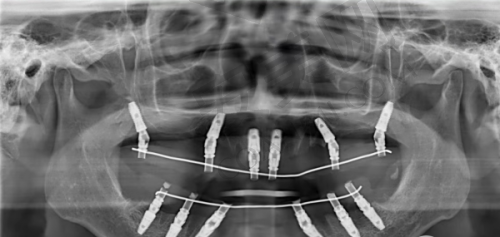

其中,主刀医生韩超在复杂口腔病例的多学科治疗设计领域积累了丰富经验,对复植修复、全口种植修复、ALL - ON4、ALL - ON6方案以及美学区种植修复均具有突出优势。他不仅能针对常规病例制定个性化方案,还能面对诸如穿颧穿翼这类解剖结构复杂的情况,利用内外提手术技术及超微创拔除等技术,处理各种疑难问题。韩超医生的代表作中包含多例全口种植重建,通过ALL - ON4和ALL - ON6方案,不仅有效修复了患者的口腔功能,更实现了面部整体美学的提升。

李明医生则在口腔种植领域有超过15年的临床经验,擅长各种种植牙技术,包括即刻种植、All - on - 4种植等。医生们术前会根据患者咬合关系、骨条件定制方案,避免“一刀切”式治疗;通过严格术前检查(如CBCT扫描)和术中导航,减少神经损伤、感染等并发症;术后还会提供定期随访服务,延长种植体使用寿命。